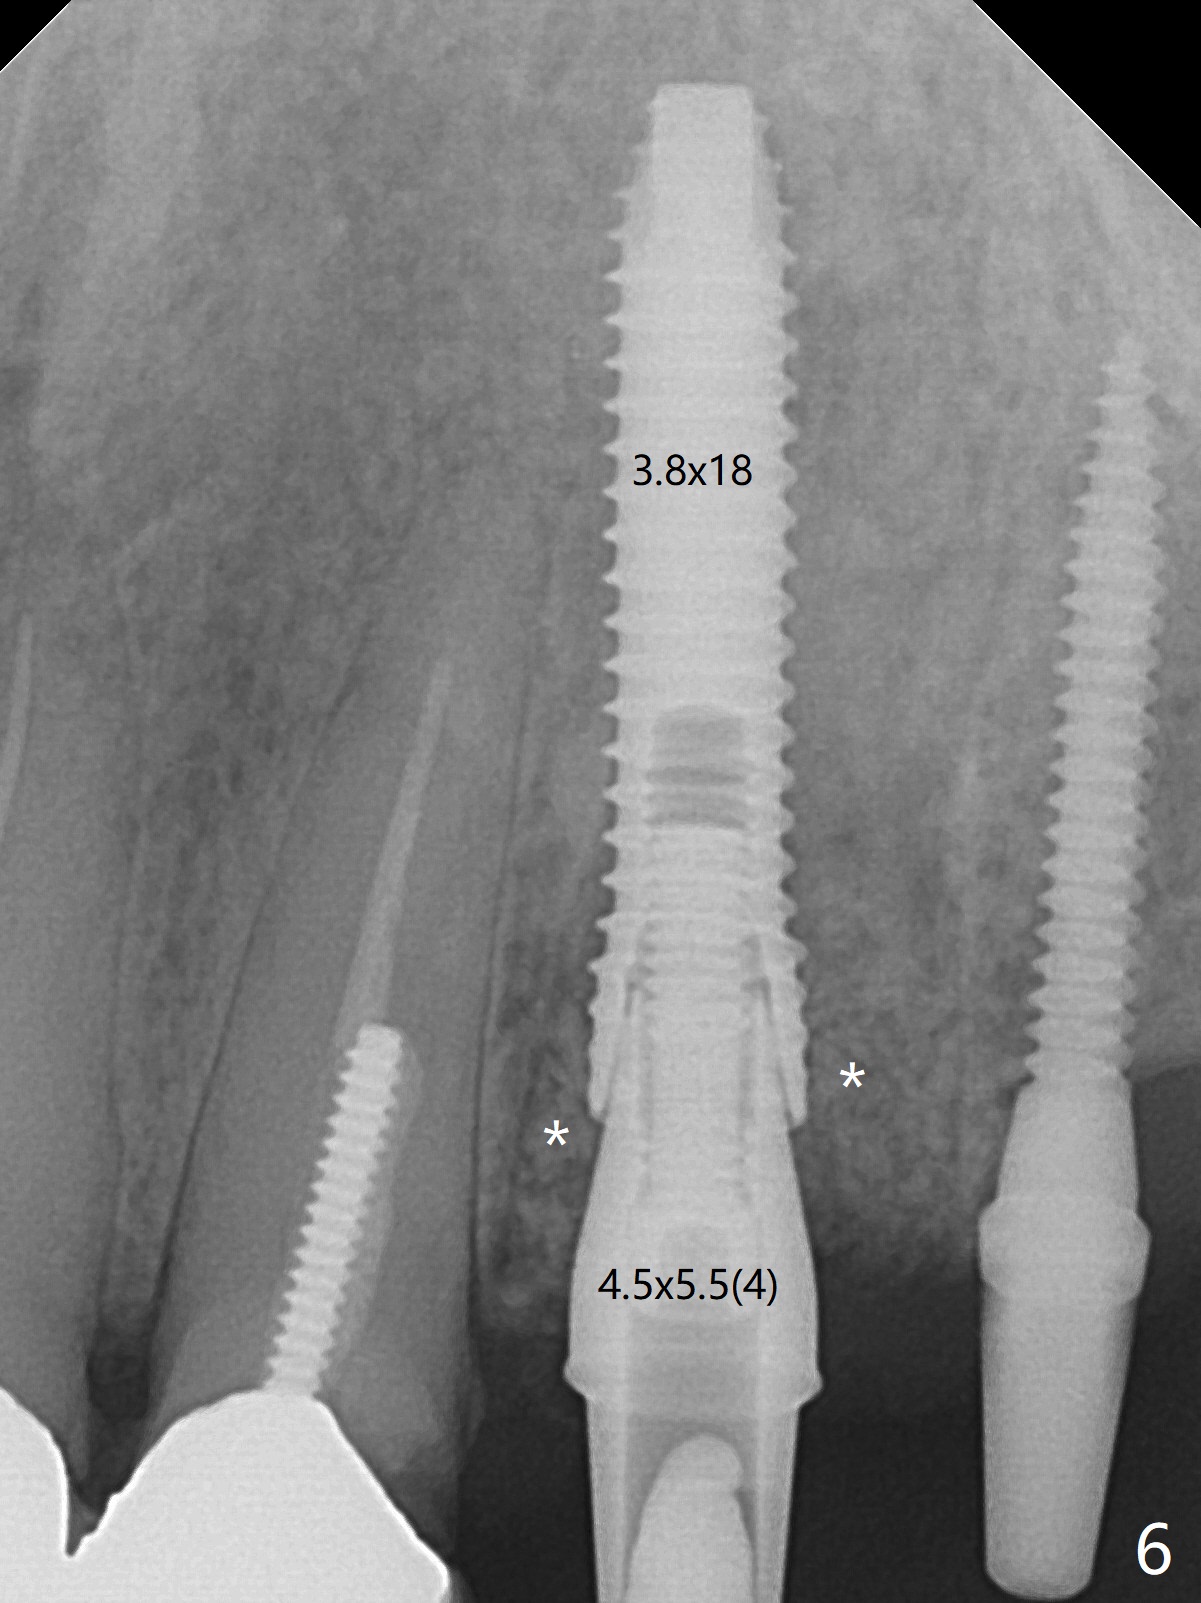

The edentulous ridge is narrow between the residual roots of #11 and 14 (Fig.1). Since the bone density is low in the edentulous area, DIO bone expanders are used (e.g., #1 (1/1.6 mm) Fig.2) after 1.2 mm initial drill. A 2x14(2) mm 1-piece implant is placed at #12 with 4 mm ridge width, while a 3x10 (2) mm dummy implant is partially placed after use of Bone Expander #2 (1.3/2.3 mm). The latter is replaced by a definitive one (3x12(2) mm), while the one at #12 is placed deeper (Fig.4). After extraction and placement of PRF and Vanilla Graft for sinus lift (Fig.4 black *), a 5x10 mm 2-piece implant is placed at #14, while a dummy implant is placed at #11 (Fig.4,5). As the osteotomy at #11 is 4.9 mm longer than the dummy (Fig.5), a definitive one is 3 mm longer (Fig.6). Osteogen plug is placed in the apical portion of each socket at #11 and 14, while Vanilla and Osteogen are packed in the coronal portion of the socket (Fig.4,6 *). Although primary stability of each implant is not high (30/40 Ncm), splinted provisional with occlusal clearance seems to be sufficient for implant osteointegration. There is no discomfort 9 days postop (Fig.7). Impression is taken 3 months postop, since he plans to return to home country for business (Fig.8). Single unit crowns are cemented 4 months postop (Fig.9,10). The abutment screw at #14 needs retightening 6 months post cementation. The access hole slightly buccal. Chewing pain at #12 is reduced after occlusal adjustment 6.5 months post cementation (Fig.11).